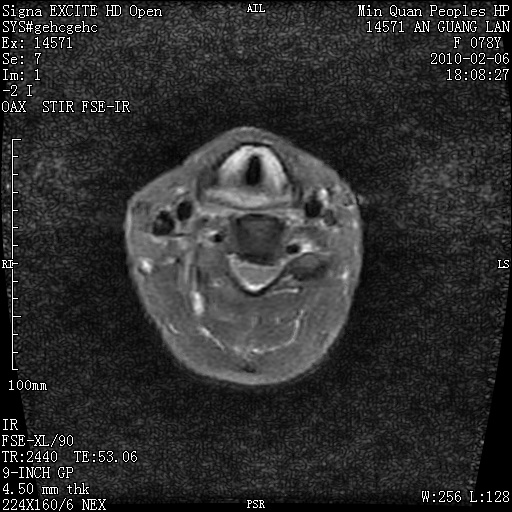

标题: MRI2763:C6、C7椎体病变性质?

f,78y,颈部与双上肢阵发性剧痛40余天。ct可见c6、c7椎体虫蚀样破坏,其间椎间隙变窄(没有图片资料可供上传)。